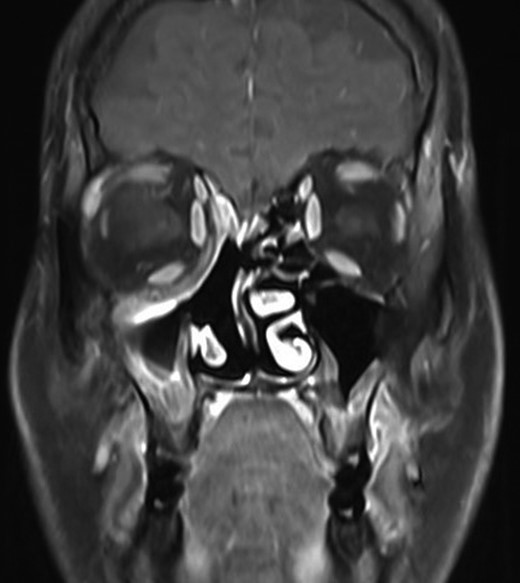

On radiological evaluation, CT scan with contrast of the paranasal sinuses (PNS) revealed a mass involving the right ethmoid sinus with medial wall and orbital floor extension (Fig. 2). The subsequent magnetic resonance imaging (MRI) revealed an infiltrative soft tissue mass occupying the right ethmoid sinus, eroding inferio-medial orbital wall and extending to the extracoanal space (Fig. 3). Positron emission tomography (PET) scan demonstrated an ill-defined 4.5 × 4.2 cm2 mass lesion in the right nasal cavity and ethmoid sinus extending to the right medial orbital floor (Fig. 4). The scan did not reveal any associated lymphadenopathies.

Magnetic resonance imaging (MRI) showing an enhancing soft tissue mass in the ethmoid sinus, eroding inferio-medial orbital wall.